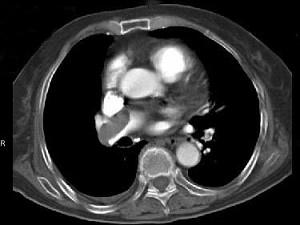

问题 82岁,女性,突发右侧胸痛,呼吸急促,行急诊CT检查,如图所示,请选择最佳答案 ( )

选项 A、肺动脉栓塞 B、肺动脉瘤 C、肺门淋巴结肿大 D、肺动静脉瘘 E、中央型肺癌

答案 A